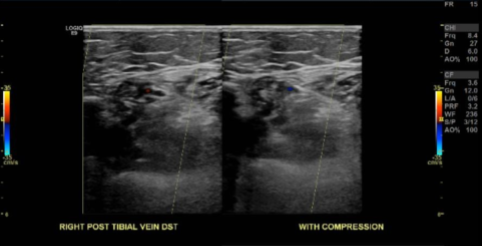

Doppler Venous Right Lower Extremity

The results showed no sonographic evidence for RIGHT lower extremity deep venous thrombosis.